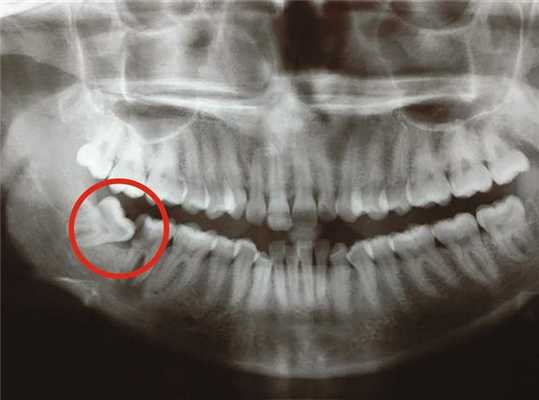

Диагностика полуретинированного зуба незатруднительна: при стоматологическом осмотре над десной выявляется верхушка зуба, контуры зуба определяются при пальпации, коронка обнаруживается при зондировании. Ретинированный зуб может быть достоверно обнаружен только с помощью прицельной рентгенографии или ортопантомографии; в некоторых случаях требуется проведение компьютерной томографии. Полуретинированный зуб с отложениями зубного налета или зубного камня может быть ошибочно принят за корень зуба, пораженный кариесом.

КТ челюстно-лицевой области (3D-реконструкция). Непрорезавшийся ретинированный клык верхней челюсти справа, расположенный под углом в толще альвеолярного отростка.

Если врач не нашел какой-то из зубов, который уже должен прорезаться у ребенка (или взрослого, если речь идет о восьмерках), он направляет пациента на рентгеновское исследование. На снимке отлично видны все нарушения и можно увидеть сформированные зубы в мягких тканях. Для уточнения положения и для последующего лечения применяют артопантомографию, создание гипсовых моделей челюстей и делают телерентгенографию.

Дистопированный зуб на рентгене